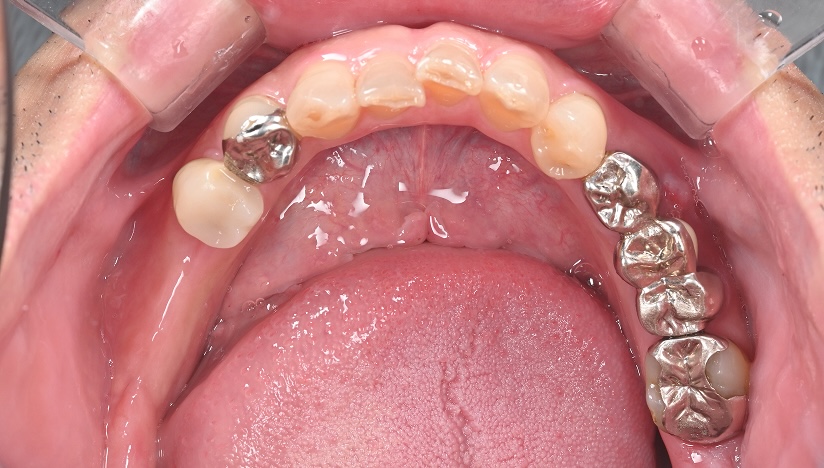

主訴

奥歯で噛めない、歯茎が腫れてきた

治療内容

抜歯即時インプラント埋入1本、待時インプラント埋入2本、リッジプリザベーション(顎堤温存術)、GBR

治療期間

6〜8ヶ月

治療費用

1,947,000

治療の

リスク

オッセオインテグレーションが得られなかった場合、撤去、再度埋入の可能性